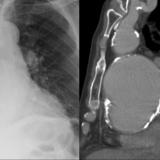

Aortic aneurysm

Date: 03/02/2014

Views: 2238